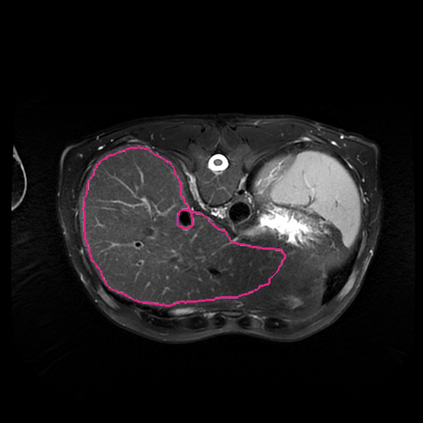

Radiomics uses quantitative medical imaging features to predict clinical outcomes. Currently, in a new clinical application, finding the optimal radiomics method out of the wide range of available options has to be done manually through a heuristic trial-and-error process. In this study we propose a framework for automatically optimizing the construction of radiomics workflows per application. To this end, we formulate radiomics as a modular workflow and include a large collection of common algorithms for each component. To optimize the workflow per application, we employ automated machine learning using a random search and ensembling. We evaluate our method in twelve different clinical applications, resulting in the following area under the curves: 1) liposarcoma (0.83); 2) desmoid-type fibromatosis (0.82); 3) primary liver tumors (0.80); 4) gastrointestinal stromal tumors (0.77); 5) colorectal liver metastases (0.61); 6) melanoma metastases (0.45); 7) hepatocellular carcinoma (0.75); 8) mesenteric fibrosis (0.80); 9) prostate cancer (0.72); 10) glioma (0.71); 11) Alzheimer's disease (0.87); and 12) head and neck cancer (0.84). We show that our framework has a competitive performance compared human experts, outperforms a radiomics baseline, and performs similar or superior to Bayesian optimization and more advanced ensemble approaches. Concluding, our method fully automatically optimizes the construction of radiomics workflows, thereby streamlining the search for radiomics biomarkers in new applications. To facilitate reproducibility and future research, we publicly release six datasets, the software implementation of our framework, and the code to reproduce this study.